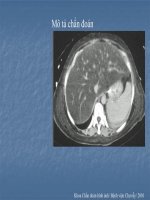

KỸ THUẬT CHỤP CT BỤNG